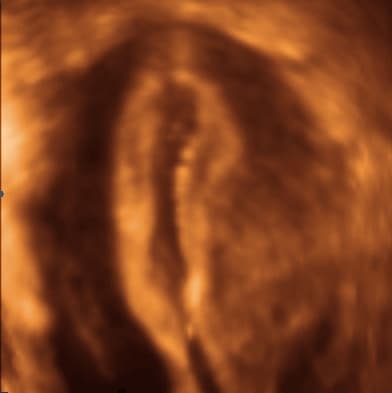

Dvoroga maternica / uterus bicornis čine dvije maternične šupljine odijeljene u cijelosti, uz jedan cerviks. Tijelo maternice je u gornjoj trećini odijeljeno dubokim utorom koji formira dva jasna roga koji se u donjoj trećini spajaju i čine jedan vrat maternice. Ukoliko imamo dvije maternične šupljine i duboki utor na tijelu maternice s vanjske strane, ali dva vrata maternice, govorimo o uterusu didelphysu / dvostrukoj maternici.

Dvostruka maternica /uterus didelphys, uterus duplex posljedica je izostanka bilo kakvog spajanja dvaju Müllerova kanala. Svaki rog maternice je potpuno razvijen i gotovo normalne veličine, postoje i dva cerviksa, a nekad i dvije vagine. Trudnoća se može dogoditi u jednom od rogova i proći relativno mirno. Abnormalnosti maternične šupljine mogu dovesti do brojnih komplikacija tijekom trudnoće kao što su malpozicije fetusa (kosi položaj, položaj zatkom...), prijevremenog prsnuća plodovih ovoja, te spontani pobačaj i prijevremeni porođaj.

Diferencijalnu dijagnostiku osobito pospješuje primjena trodimenzionalnog i kontrastnog ultrazvuka, kada se u materište instilira fiziološka otopina ili kontrast koja se potom pregledava u svim dimenzijama. Kontrastni ultrazvuk ne samo da je koristan u evaluaciji kongenitalnih anomalija uterusa, već omogućuje i ispitivanje prohodnosti jajovoda. Za trodimenzionalni ultrazvuk se kaže da nalazi uterusa koreliraju s vanjskom konfiguracijom uterusa nađenom pri laparoskopiji, da mu je osjetljivost i specifičnost 100% za dijagnozu velikih anomalija Müllerovih cijevi, i 100% preciznost za bikornualni uterus.